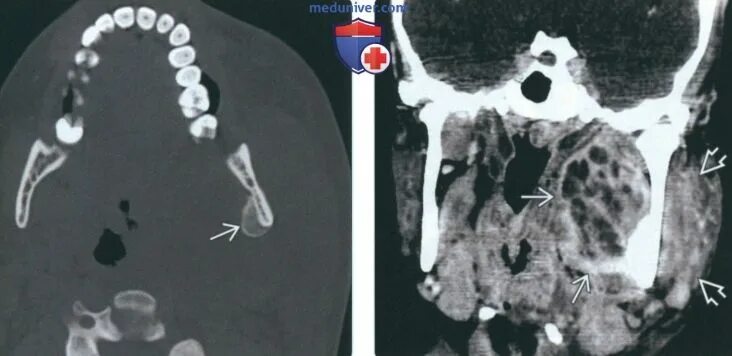

Абсцесс челюстного пространства